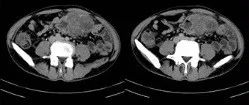

中年男性,头晕乏力、腹泻半月,请诊断!

医学影像  yxyx-app  医学影像APP,打造伴随医生快速成长的影像学习社区。与影像园(Xctmr.com)一起提供最全面的影像案例库、基础(解剖、病理、影像诊断)知识、影像技术及考题等,为医生提供最佳的医学影像参考。【所属科室】消化科【基本资料】患者,男,48岁【主诉】头晕,乏力,腹泻半月【实验室检查】CEA:8.86ng/ml,CA211:4.51,CA724:22.07...